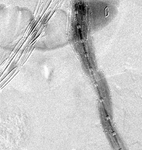

Resolution of the type I endoleak resolved after extension deployed

University of Michigan, specifically the cases of Dr Upchurch reflecting the Departments of Vascular Surgery and Radiology